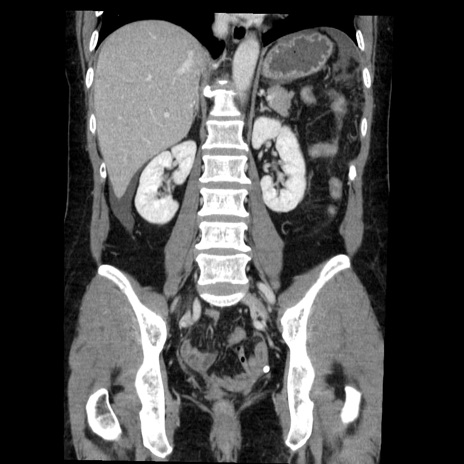

症例6(冠状断像)

【症例】50歳代女性

【主訴】下腹部痛

【現病歴】本日朝より下痢2回あり。 昼食を食べた後、嘔吐3回、下腹部痛認め、症状軽快せず、当院救急搬送。

最終食事:本日昼(生ものなし)。 昨日の夜、刺身を食ぺたとのこと。周囲に同様の症状の者なし。普段、排便は毎日あるとのこと。

【既往歴】卵巣癌術後(8年前に当院で卵巣摘出)

【身体所見】 意識清明、腹部:平坦、腸蠕動音→、やや硬、下腹部自発痛・圧痛あり、反跳痛あり、筋性防御なし。

【データ】WBC 16000、CRP 0.01